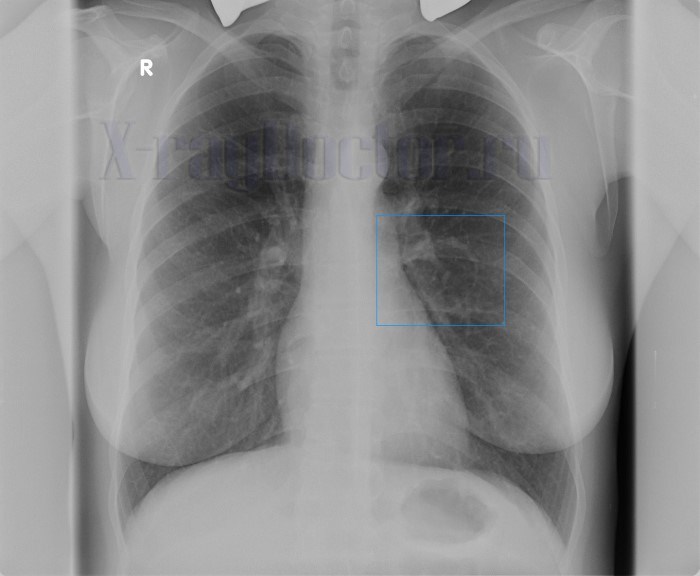

Ретенционная киста легкого на рентгеновском снимке выявляется по следующим признакам:

- Тонкостенная округлая тень.

- Неровный наружный контур за счет соединительной ткани.

- При наличии воздуха внутри полости прослеживается уровень жидкости.

Ретенционные кисты образуются при закупорке бронха мокротой, опухолью и инородным телом. При этом вздувается проксимальная часть бронхиального дерева. На рентгенограмме образование представлено кольцевидной тенью неправильной овальной формы, которое с одной стороны имеет дугообразное закругление (место закупорки).

Синдром кольцевидной тени на снимке определяется по следующим рентген-симптомам:

- овальное или веретенообразное затемнение с двумя «рогами», сформированными мелкими бронхами;

- двугорбая тень;

- многочисленные выпячивания стенки растянутых бронхов (ретенционная киста);

- колбообразные затемнения, «грозди винограда», реторты.

Ретенционная форма образования имеет вид «ветки дерева» — один центр с многочисленными разветвлениями. Из-за специфичности строения контуры полости полициклические, волнистые или бугристые и тонкие. Вокруг тени деформируется легочной рисунок. На снимках, выполненных в разные фазы дыхательного цикла, форма и контуры образования не изменяются.

Киста легкого на рентгенограмме обычно выглядит как округлое или овальное образование с четкими контурами, обычно с тонкой стенкой. Она может быть одиночной или множественной, и ее размеры могут варьироваться.